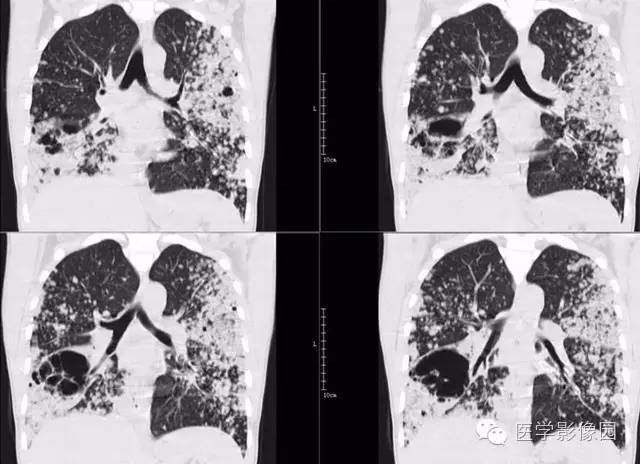

弥漫性肺泡细胞癌1例CT影像表现

病理结果:弥漫性肺泡细胞癌

弥漫性肺泡癌的主要临床及CT表现:临床表现无明显特征, 随着病情的进展, 咳嗽、 咳白痰、 进行性气促。CT表现 为病变分布有两种情况:病变累及一个肺段或肺叶;病变广泛分布于两肺。可归纳为5个特征性征象:蜂房征;支气管充气征;磨玻璃征;血管造影征;两肺弥漫分布的斑片状与结节影。